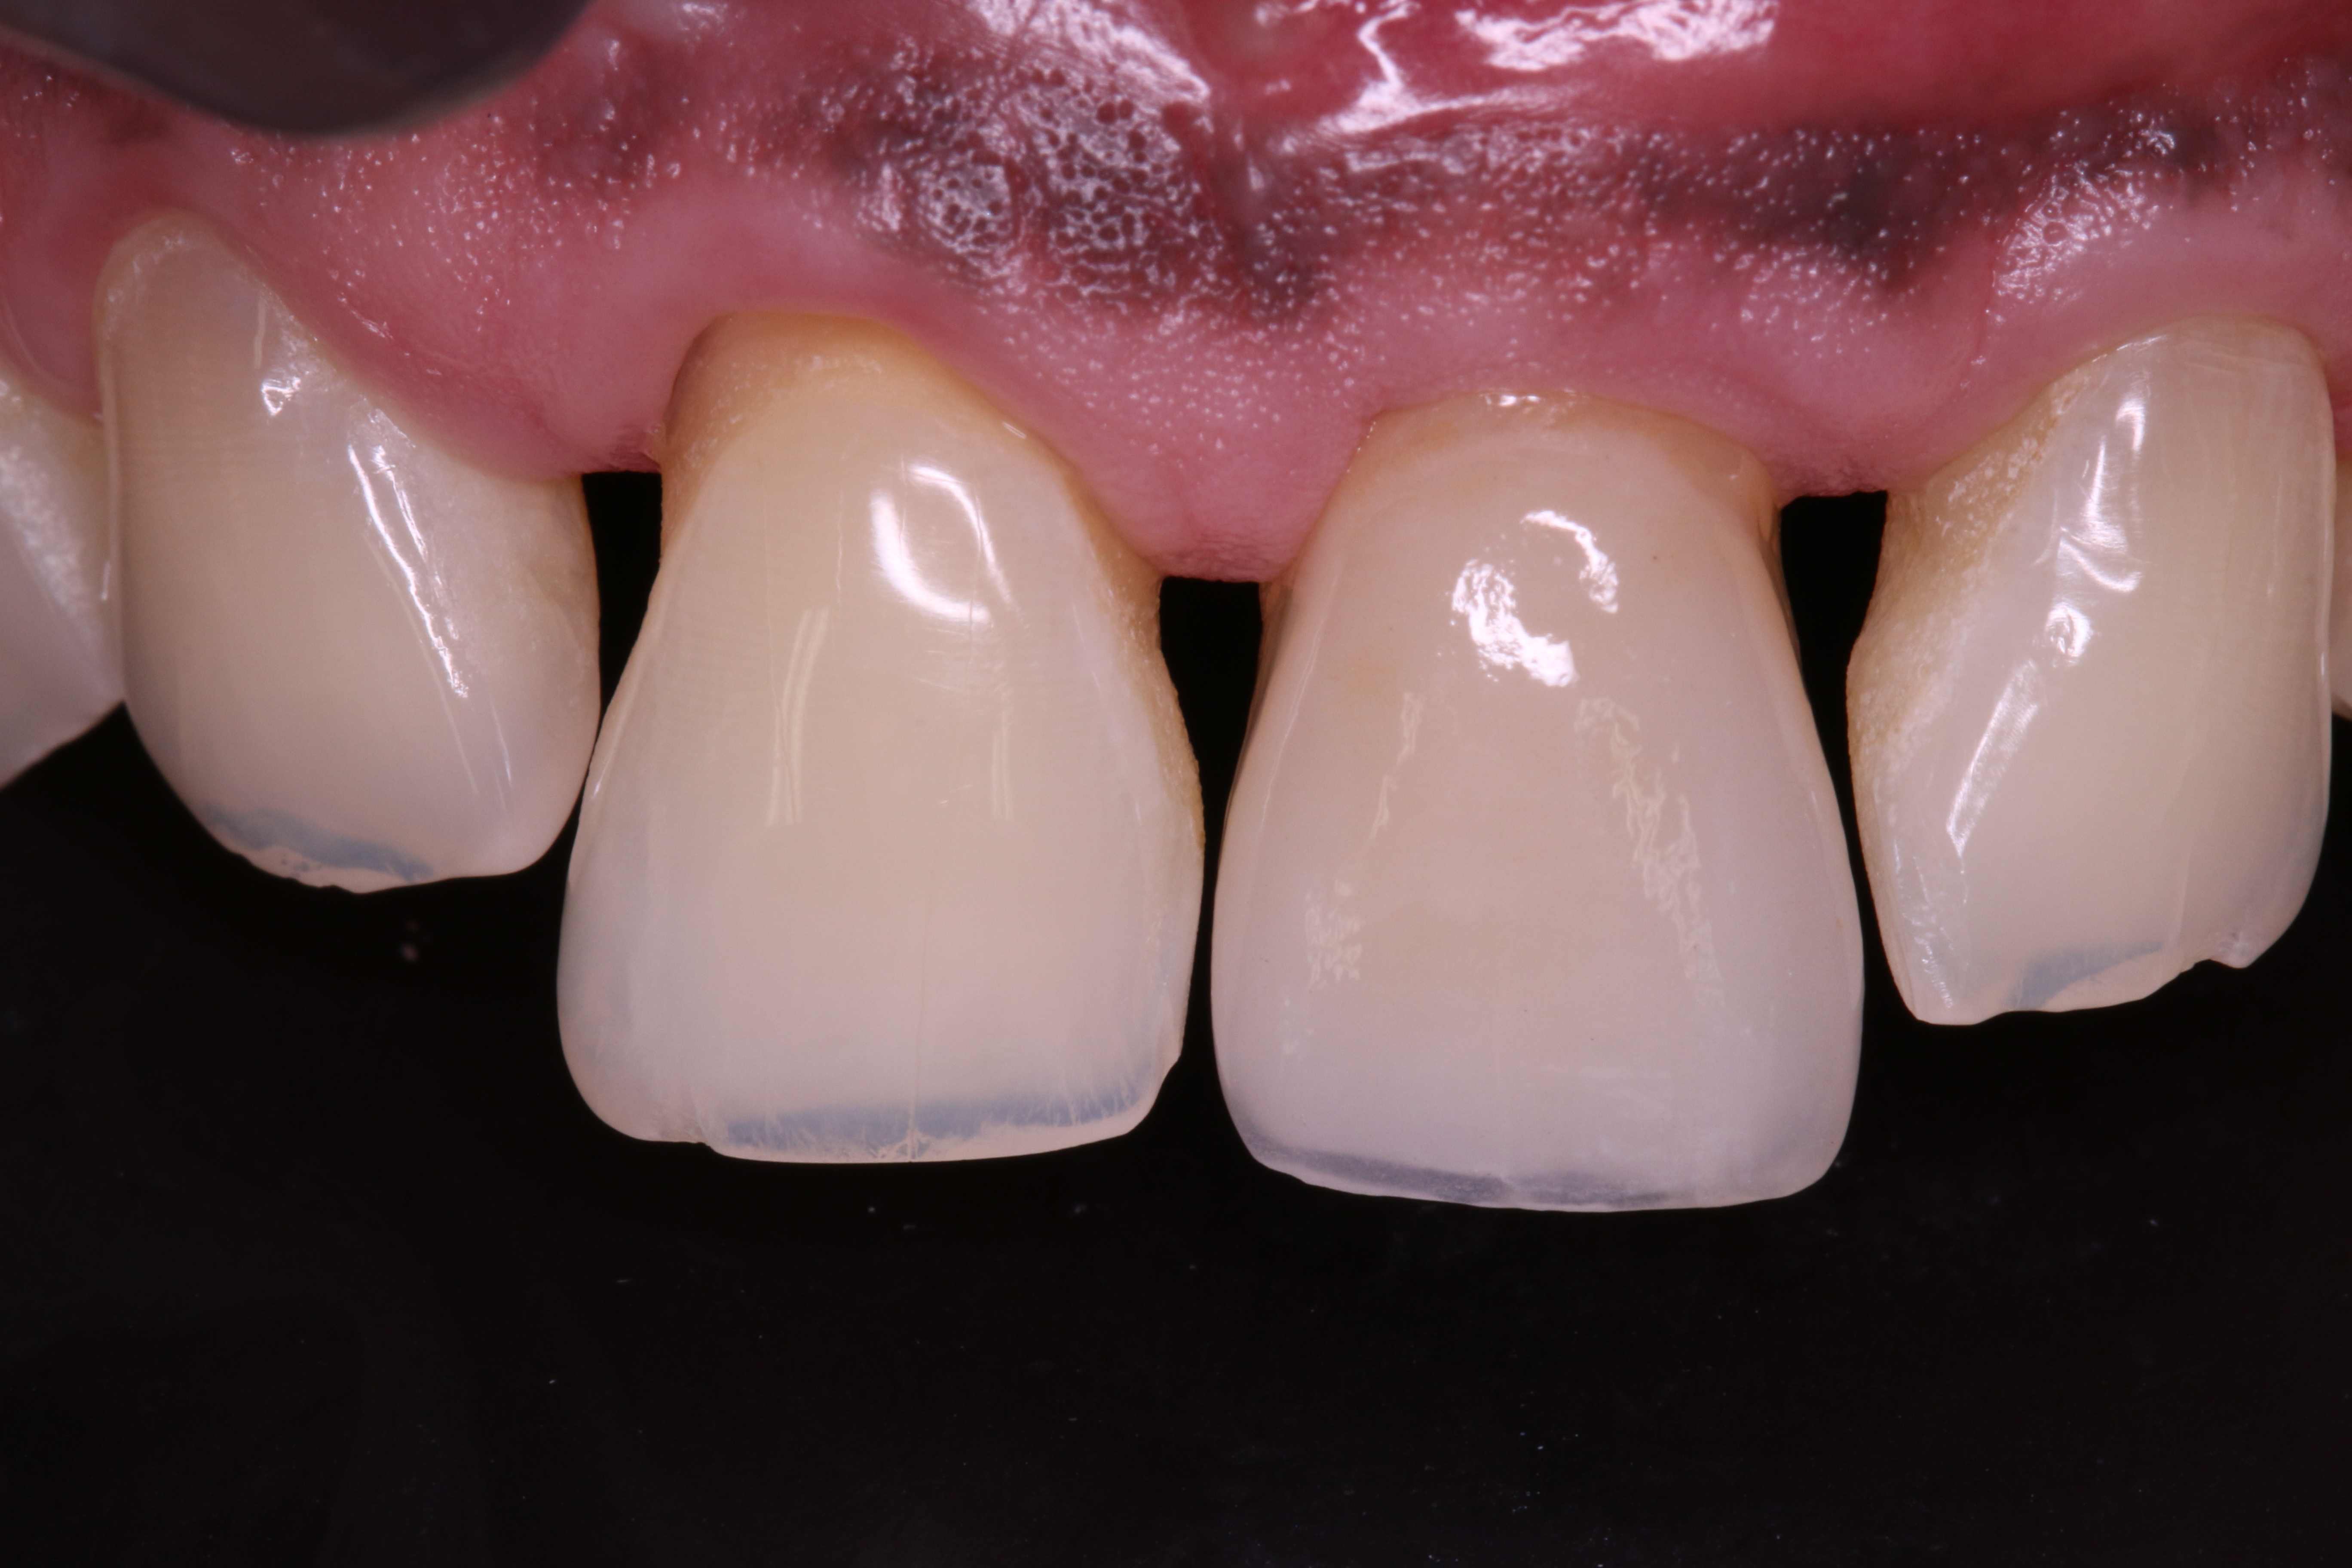

01/19 - Initial clinical situation with gum recession and labial bone loss eight weeks following tooth extraction

GBR with cerabone® and Jason® membrane in the front tooth region - Dr. H. Maghaireh